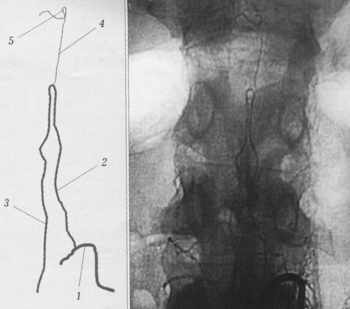

Рис. 1. Схема операции свободной оментомиелопексии.

а - микроанастомозы с межреберной артерией и веной;

б - микроанастомозы с затылочной артерией и веной.

Рис. 2. Схема операций перемещения межреберного

сосудисто-нервного пучка на дистальные отделы спинного мозга со свободной

оментомиелопексией.

Рисунки В.В. Троценко

У всех пациентов выполняли спинальную ангиографию, ангиографию межреберных

артерий, у больных с локализацией травмы в шейном или верхнегрудном отделе позвоночника

- ангиографию затылочных артерий. Особое внимание уделяли исследованию кровоснабжения

в области травмы спинного мозга. Для этого применяли спинальную ангиографию

по методике Т.П. Тиссена [6]. При травме шейного отдела спинного мозга производили

селективную катетеризацию с контрастированием спинальных артерий. Контрастное

вещество вводили вручную до появления изображения передних радикуломедуллярных

артерий. Исследование заканчивали после получения полного изображения передней

спинальной артерии в зоне травмы и выше- и нижележащих отделов спинного мозга

(рис.3). При анализе ангиограмм определяли локализацию артерии Адамкевича,

уровень ее отхождения от соответствующей межреберной или поясничной артерии,

сторону отхождения, а также кровоснабжаемый ею бассейн передней спинальной артерии.

Рис. 3. Спинальная ангиограмма больного Л. 29 лет.

Окклюзия передней спинальной артерии.

1 - поясничнаая артерия L1; 2 - артерия Адамкевича; 3 - нисходящий отдел

передней спинальной артерии; 4 - восходящий отдел передней спинальной

артерии; 5 - окклюзия передней спинальиой артерии. |